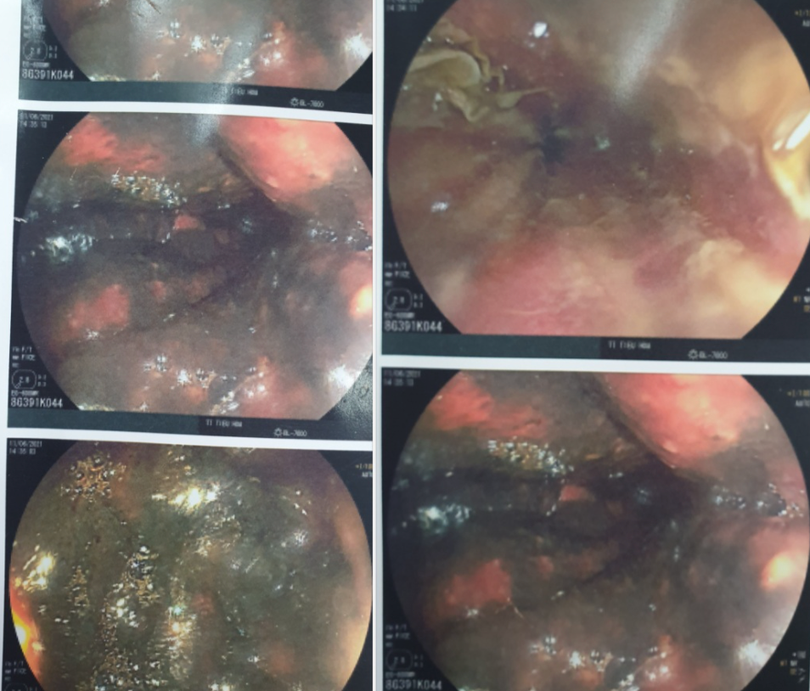

Kết quả nội soi toàn bộ đường tiêu hóa của bệnh nhân cho thấy niêm mạc thực quản bị phù nề xung huyết, có loét nông kèm theo giả mạc trắng, long tróc biểu mô thực quản. Dạ dày bệnh nhân có nhiều dịch đen bẩn. Toàn bộ niêm mạc dạ dày viêm loét phù nề xung huyết mạnh. Niêm mạc hành tá tràng và tá tràng cũng viêm loét phù nề, xung huyết mạnh.

Hiện, bệnh nhân đang được theo dõi sát sao, duy trì dinh dưỡng, kháng sinh. Sau 2 tuần nữa, bệnh nhân sẽ được nội soi lại toàn bộ đường tiêu hóa để có hướng điều trị tiếp theo.